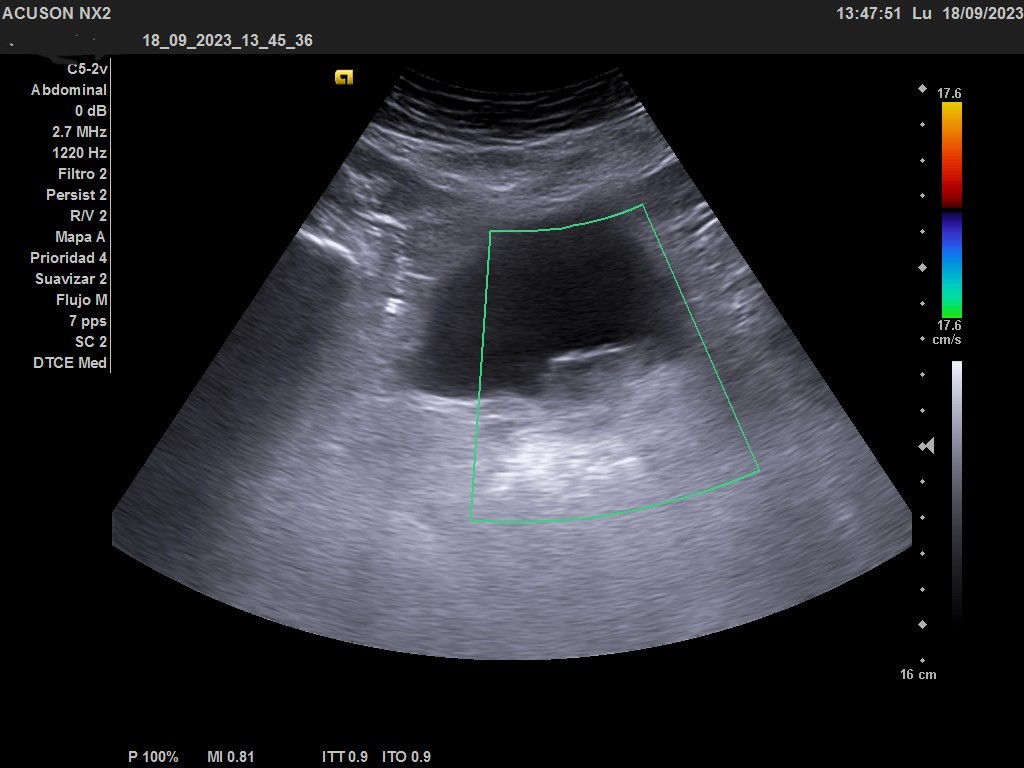

Hallazgos ecográficos

Ecografía clínica urológica: vejiga moderadamente replecionada. Se visualiza en pared posterior imagen hiperecogénica que no capta al Doppler color, de características sospechosas de malignidad. Riñones sin alteraciones en parénquima ni signos de hidronefrosis.

En la ecografía urológica reglada ambos riñones son de tamaño normal y parénquima conservado. La vejiga está replecionada, pero se identifica un engrosamiento nodular de 26 x 15 mm en la pared inferolateral izquierda, próxima al meato. Próstata de pequeño tamaño con un volumen de 7 cc.

Orientación diagnóstica de tumor vesical.